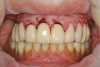

A 70-year-old woman presented requesting that her maxilla be restored with a fixed restoration. Her past medical history was noncontributory (American Society of Anesthesiologists [ASA] I). A comprehensive dental examination was performed, which included hard- and soft-tissue charting, periodontal charting with mobility of her remaining maxillary teeth, and a radiographic series. She was missing all maxillary molar and second premolar teeth (Figure 1 and Figure 2). Her remaining maxillary teeth had grade 1 to grade 2 mobility with probing depths of 2 mm to 8 mm.

She used a removable partial denture, which was stable and fit well, to replace her missing maxillary posterior teeth. A CBCT scan (Fig- ure 3) and intraoral surface scans, including maxillary, mandibular, and centric record scans, were taken (Figure 4 and Figure 5). The prognosis of her remaining maxillary teeth was poor with a very low probability of any reasonable long-term success for a maxillary full-arch fixed restoration utilizing her maxillary teeth.

Fig 1. The patient’s clinical appearance pretreatment. The patient used maxillary and mandibular removable partial dentures to replace her missing posterior teeth.

Fig 2. Pretreatment panoramic radiograph. Note extensive sinus pneumatization.

Fig 3. Extensive bone loss was present around the maxillary anterior teeth.